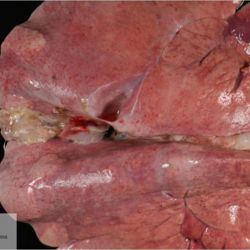

Pàgina anterior de 637 Pàgina següent 3181 total Ovine Specie: Ovine Organ: Brain Lesion: Meningitis Lesion modifier: Meningitis - Fibrinous-purulent Disease: - Not viewed Ovine Specie: Ovine Organ: Lung Lesion: Atelectasis Lesion modifier: - Disease: - Files/Expedient: Leon15 Position: 136 (2 views) Ovine Specie: Ovine Organ: Lung Lesion: Atelectasis Lesion modifier: - Disease: - Files/Expedient: Leon15 Position: 87 (3 views) Ovine Specie: Ovine Organ: Lung Lesion: Bronchitis Lesion modifier: - Disease: Dictyocaulosis Files/Expedient: Leon12 Position: 253 (1 views) Bovine Specie: Bovine Organ: Lung Lesion: Bronchopneumonia Lesion modifier: Bronchopneumonia - Catarrhal-purulent Disease: - Position: 253 (1 views) Pàgina anterior de 637 Pàgina següent Títol Select...Avian (Exotic) (110)Avian (Poultry) (76)Bovine (317)Canine (935)Caprine (47)Equine (257)Feline (326)Ferret (19)General (127)Marine mammal (22)Non-human primate (20)Ovine (328)Porcine (379)Rabbit (61)Reptile (38)Rodent (28)Wildlife (91) Format Select...- (60)Abomasum (37)Adrenal gland (10)Blood (7)Blood vessel (50)Body as a whole (19)Bone (57)Bone marrow (21)Brain (93)Cloaca (1)Diaphragm (2)Ear (5)Esophagus (39)Eye (16)Fetus (12)Gallbladder (23)Gizzard (2)Heart (265)Intestine (356)Joint (32)Kidney (443)Larynx (5)Liver (326)Lung (264)Lymph node (91)Mammary gland (10)Mediastinum (1)Muscle (22)Nasal cavity (22)Nerve (7)Omasum (5)Oral cavity (63)Ovary (14)Oviduct (8)Pancreas (7)Parathyroid (5)Penis (10)Peritoneum (65)Pharynx (9)Pituitary gland (6)Placenta (7)Prostate (8)Proventriculus (3)Reticulum (1)Rumen (28)Sinus (7)Skin (181)Spinal cord (15)Spleen (105)Stomach (125)Teeth (1)Testicle (11)Thoracic cavity (31)Thymus (13)Thyroid gland (5)Tongue (32)Tonsils (11)Trachea (11)Urethra (5)Urinay bladder (61)Uterus (27)Vagina (1)Vulva (1)Yolk sac (1) Cobertura Select...- (152)Abomasitis (26)Abscess (27)Acidosis (1)Adenocarcinoma (20)Adenoma (9)Aerosacculitis (6)Agenesis (1)Agnathia (1)Alopecia (7)Amyloidosis (12)Aneurysm (6)Angiectasis (1)Anthracosis (1)Arteritis (11)Arthritis (15)Arthrogryposis (6)Artifact (4)Ascites (13)Atelectasis (8)Atherosclerosis (5)Atresia (1)Atrial septal defect (2)Atrophy (10)Autolysis (7)Bronchitis (6)Bronchopneumonia (26)Cachexia (2)Carcinoma (103)Cardiomyopathy (19)Cellulitis (2)Chemodectoma (4)Cholangiohepatitis (4)Cholangitis (19)Cholecystitis (4)Cholestasis (5)Chondrodysplasia (2)Chondrosarcoma (2)Chronic passive congestion (13)Chylothorax (2)Cirrhosis (6)Coelomitis (3)Coenurus cerebralis (4)Colitis (40)Congestion (17)Conjunctivitis (5)Coronitis (3)Cryptorchidism (3)Cyst (25)Cystitis (24)Dermatitis (69)Diaphragmatic hernia (4)Dilation (28)Discospondylitis (1)Disseminated intravascular coagulation (7)Dyschondroplasia (1)Dysplasia (29)Ectopia cordis (1)Ectopic ureter (1)Edema (55)Emphysema (5)Encephalitis (5)Endocardiosis (14)Endocarditis (26)Endometritis (5)Enteritis (118)Enterolith (6)Epulis (3)Esophagitis (14)Fasciitis (1)Fibrosis (7)Fibrous osteodystrophy (8)Fistula (1)Folliculitis (3)Fracture (2)Gastritis (34)Gingivitis (5)Glioma (8)Glomerulonephritis (21)Glossitis (25)Glycogenosis (1)Gout (8)Granuloma (2)Granulosa cell tumor (4)Hemangioma (9)Hemangiosarcoma (46)Hematoma (8)Hemoglobinuria (2)Hemopericardium (12)Hemoperitoneum (2)Hemorrhage (100)Hemosiderosis (7)Hemothorax (2)Hepatitis (78)Hernia (11)Histiocytosis (3)Hydatid cyst (11)Hydrocephalus (9)Hydrometra (1)Hydronephrosis (22)Hydropericardium (6)Hydrothorax (3)Hydroureter (5)Hyperkeratosis (8)Hyperostosis (4)Hyperplasia (37)Hypertrophy (9)Hypopigmentation (1)Hypoplasia (7)Hypopyon (1)Impaction (6)Infarction (63)Insulinoma (6)Intussusception (5)Jaundice (17)Laminitis (2)Laryngitis (2)Leiomyoma (5)Leukemia (13)Lipidosis (36)Lipoma (7)Lymphadenitis (45)Lymphadenopathy (7)Lymphangiectasia (6)Lymphangitis (5)Lymphoma (221)Malacia (11)Malignant melanoma (15)Mast cell tumor (11)Mastitis (8)Megaesophagus (2)Melanosis (3)Melena (4)Meningioma (6)Meningitis (6)Meningocele (2)Meningoencephalitis (5)Mesothelioma (5)Methemoglobinemia (2)Mineralization (10)Mucocele (5)Mucometra (1)Multilobular bone tumor (1)Mummification (3)Myelofibrosis (1)Myocarditis (4)Myositis (5)Necrosis (81)Nephritis (113)Nephroblastoma (6)Nephrosclerosis (1)Nephrosis (14)Neuritis (1)Obstruction (13)Omasitis (4)Omphalitis (1)Omphalophlebitis (7)Orchitis (4)Osteoarthrosis (5)Osteomyelitis (9)Otitis (2)Palatoschisis (3)Pancreatitis (3)Panniculitis (3)Papilloma (7)Parakeratosis (14)Patent ductus arteriosus (6)Peliosis hepatis (1)Perforation (17)Pericarditis (35)Peritonitis (39)Persistent right aortic arch (1)Pharyngitis (2)Pheochromocytoma (2)Phlebitis (2)Placentitis (6)Pleuritis (21)Pleuropneumonia (24)Pneumonia (109)Pneumothorax (3)Polycystosis (14)Polyp (5)Polyserositis (6)Posthitis (1)Proctitis (4)Prolapse (3)Prostatitis (3)Proventriculitis (1)Pyelonephritis (24)Pyometra (6)Pyothorax (4)Rhinitis (11)Rumenitis (6)Rupture (24)Salpingitis (3)Sarcoma (57)Sclerosis (1)Scoliosis (2)Seminoma (2)Sequestrum (2)Serous atrophy (14)Sinusitis (7)Splenitis (14)Splenomegaly (9)Spondylitis (6)Spondylosis (1)Stenosis (9)Stomatitis (32)Tenosynovitis (2)Teratoma (3)Thricobezoar (2)Thrombosis (16)Tonsilitis (4)Torsion (13)Tracheitis (4)Tympany (7)Typhlitis (8)Typhlocolitis (4)Ulcer (43)Urethritis (1)Urolithiasis (36)Uroperitoneum (1)Uveitis (1)Vasculitis (15)Ventricular septal defect (3)Volvulus (11) Matèria Select... - (14)- (1653)- (152)Abomasitis - Catarrhal (2)Abomasitis - Catarrhal-hemorrhagic (1)Abomasitis - Chronic (1)Abomasitis - Fibrinous-necrotizing (2)Abomasitis - Hyperplasic (5)Abomasitis - Hyperplasic - Chronic (1)Abomasitis - Necrotic (1)Abomasitis - Necrotizing (2)Abomasitis - Ulcerative (5)Adenocarcinoma (9)Aerosacculitis - Granulomatous (1)Amyloidosis - Chronic (1)Arteritis - Necrotic (2)Arteritis - Necrotizing (1)Arthritis - Chronic (4)Arthritis - Fibrinous-purulent (3)Arthritis - Serous (4)Arthritis - Subacute (1)Ascites - Serous (1)Atrophy - Serous (1)Bronchitis - Catarrhal (3)Bronchitis - Suppurative (1)Bronchopneumonia - Catarrhal-purulent (17)Bronchopneumonia - Fibrinous (1)Bronchopneumonia - Granulomatous (1)Bronchopneumonia - Purulent (1)Bronchopneumonia - Suppurative (5)Carcinoma - Adenocarcinoma (33)Carcinoma - Adenocarcinoma - Hepatocellular (2)Carcinoma - Adenocarcinoma - Mucinous (1)Carcinoma - Basosquamous (1)Carcinoma - Cholangiocellular (3)Carcinoma - Hepatocellular (4)Carcinoma - Metastatic (3)Carcinoma - Squamous cell carcinoma (13)Carcinoma - Transitional cell (2)Cardiomyopathy - Dilated (13)Cardiomyopathy - Hypertrophic (6)Cellulitis - Necrotizing (1)Cholangitis - Chronic (8)Cholangitis - Hyperplasic (3)Cholecystitis - Fibrinous-necrotizing (1)Coelomitis - Fibrinous (1)Coelomitis - Granulomatous (1)Colitis - Catarrhal (3)Colitis - Catarrhal-hemorrhagic (1)Colitis - Fibrinous (1)Colitis - Fibrinous-necrotizing (1)Colitis - Fibrinous-necrotizing (Diphtheritic) (6)Colitis - Granulomatous (2)Colitis - Hemorrhagic (4)Colitis - Hemorrhagic-necrotizing (3)Colitis - Necrotizing (2)Colitis - Ulcerative (6)Congestion - Chronic (2)Conjunctivitis - Hyperplasic (1)Conjunctivitis - Purulent (3)Coronitis - Ulcerative (1)Cystitis - Chronic (3)Cystitis - Fibrinous (1)Cystitis - Fibrinous-necrotizing (1)Cystitis - Follicular (1)Cystitis - Hemorrhagic (6)Cystitis - Hemorrhagic-ulcerative (1)Cystitis - Necrotizing (9)Cystitis - Perforated (1)Dermatitis - Granulomatous (14)Dermatitis - Hyperkeratotic (10)Dermatitis - Hyperplasic (proliferative) (1)Dermatitis - Hyperplastic (10)Dermatitis - Necrotizing (4)Dermatitis - Pustular (4)Dermatitis - Ulcerative (2)Dilation - Chronic (1)Discospondylitis - Necrotizing (1)Dysplasia - Follicular (5)Edema - Interstitial (6)Emphysema - Interstitial (1)Encephalitis - Granulomatous (1)Encephalitis - Nonsuppurative (1)Endocardiosis - Mitral (7)Endocardiosis - Mitral - Chronic (5)Endocarditis - Valvular (6)Endocarditis - Valvular - Mitral (7)Endocarditis - Valvular - Pulmonic (1)Endocarditis - Valvular - Subacute (1)Endocarditis - Valvular - Subaortic (5)Endocarditis - Valvular - Tricuspid (4)Endometritis - Purulent (3)Endometritis - Purulent-hemorrhagic (2)Enteritis - Catarrhal (23)Enteritis - Catarrhal - Acute (1)Enteritis - Catarrhal-hemorrhagic (5)Enteritis - Catarrhal-hemorrhagic - Acute (2)Enteritis - Fibrinous (16)Enteritis - Fibrinous - Acute (3)Enteritis - Fibrinous-necrotizing (7)Enteritis - Granulomatous (14)Enteritis - Granulomatous - Chronic (1)Enteritis - Granulomatous - Multifocal (1)Enteritis - Hemorrhagic (17)Enteritis - Hemorrhagic - Acute (1)Enteritis - Hemorrhagic-necrotizing (1)Enteritis - Hyperplasic (proliferative) (4)Enteritis - Necrotizing (4)Enteritis - Necrotizing - Acute (1)Enteritis - Necrotizing - Hemorrhagic (1)Enteritis - Necrotizing-ulcerative (2)Enteritis - Ulcerative (1)Enteritis - Ulcerative-hemorrhagic (1)Esophagitis - Erosive-ulcerative (6)Esophagitis - Necrotizing (4)Esophagitis - Ulcerative (1)Esophagitis - Ulcerative-necrotizing (1)Fasciitis - Fibrinous-purulent (1)Folliculitis - Purulent (2)Gastritis - Catarrhal (2)Gastritis - Chronic (1)Gastritis - Follicular (1)Gastritis - Hemorrhagic (2)Gastritis - Hemorrhagic-necrotizing (1)Gastritis - Hypertrophic (2)Gastritis - Inclusion bodies (1)Gastritis - Mineralization (1)Gastritis - Mycotic (1)Gastritis - Necrotizing (2)Gastritis - Ulcerative (6)Gastritis - Uremic (3)Gingivitis - Erosive (2)Gingivitis - Hyperplasic (proliferative) (1)Gingivitis - Necrotizing (1)Glomerulonephritis - Chronic (7)Glomerulonephritis - Membranoproliferative (3)Glomerulonephritis - Membranoproliferative - Chronic (1)Glomerulonephritis - Membranous (3)Glomerulonephritis - Membranous - Chronic (1)Glomerulonephritis - Proliferative (2)Glomerulonephritis - Subacute (1)Glossitis - Erosive (2)Glossitis - Granulomatous (6)Glossitis - Hyperplasic (1)Glossitis - Hyperplasic (proliferative) (2)Glossitis - Hyperplastic (1)Glossitis - Necrotizing (2)Glossitis - Necrotizing - Focal (1)Glossitis - Ulcerative (6)Glossitis - Ulcerative - Multifocal (1)Glossitis - Ulcerative - Subacute (1)Glycogenosis (1)Granuloma - Eosinophilic (1)Hemangiosarcoma - Metastatic (2)Hemorrhage - Acute (1)Hemorrhage - Subcapsular (3)Hepatitis - Abscess (9)Hepatitis - Acute (3)Hepatitis - Chronic (4)Hepatitis - Chronic interstitial (6)Hepatitis - Granulomatous (7)Hepatitis - Interstitial - Multifocal (1)Hepatitis - Interstitial - Subacute (1)Hepatitis - Necrotizing (17)Hepatitis - Necrotizing - Acute (2)Hepatitis - Necrotizing - Hemorrhagic (1)Hepatitis - Necrotizing - Subacute (1)Hepatitis - Pyogranulomatous (7)Hepatitis - Subacute (4)Hydronephrosis - Chronic (1)Hydropericardium - Chronic (1)Hyperplasia - Erythroid (1)Hyperplasia - Lymphoid (3)Hyperplasia - Myeloid (1)Hyperplasia - Nodular (8)Hypertrophy - Concentric (2)Hypertrophy - Eccentric (3)Infarction - Acute (17)Infarction - Acute - Multifocal (2)Infarction - Chronic (5)Infarction - Chronic - Multifocal (1)Infarction - Subacute (18)Infarction - Subacute - Focal (2)Laminitis - Chronic (2)Laryngitis - Necrotic (1)Laryngitis - Necrotizing (1)Leukemia - Lymphoid leukemia (2)Leukemia - Non-lymphoid leukemia (6)Lipidosis - Multifocal (1)Lipidosis - Panlobular (1)Lipidosis - Panlobular - Generalized (2)Lymphadenitis - Granulomatous (24)Lymphadenitis - Granulomatous - Chronic (3)Lymphadenitis - Hemorrhagic (1)Lymphadenitis - Necrotizing (5)Lymphadenitis - Necrotizing (caseous) (11)Lymphangitis - Granulomatous (1)Lymphangitis - Purulent (1)Lymphangitis - Ulcerative (1)Lymphoma - Alimentary lymphoma (7)Lymphoma - Cutaneous lymphoma (6)Lymphoma - Lymphosarcoma (2)Lymphoma - Mediastinal lymphoma (1)Lymphoma - Multicentric lymphoma (29)Malignant melanoma - Malignant (1)Malignant melanoma - Metastatic (1)Mast cell tumor - Metastatic (1)Mastitis - Fibrinous-purulent (2)Mastitis - Necrotic (1)Mastitis - Purulent (3)Mastitis - Suppurative (1)Meningitis - Fibrinous-purulent (2)Meningitis - Purulent (4)Meningoencephalitis - Necrotizing (3)Meningoencephalitis - Nonsuppurative (2)Mineralization - Metastatic (4)Myocarditis - Fibrous - Chronic (1)Myocarditis - Granulomatous (1)Myositis - Purulent (2)Necrosis - Acute (1)Necrosis - Cortical (5)Necrosis - Follicular (1)Necrosis - Papillary (8)Necrosis - Papillary - Acute (3)Necrosis - Subacute (3)Necrosis - Tubular (6)Nephritis - Embolic (2)Nephritis - Embolic suppurative (7)Nephritis - Granulomatous (27)Nephritis - Granulomatous - Chronic (1)Nephritis - Granulomatous - Multifocal (1)Nephritis - Interstitial (6)Nephritis - Interstitial - Acute (4)Nephritis - Interstitial - Chronic (41)Nephritis - Interstitial - Subacute (12)Nephritis - Purulent (7)Nephritis - Purulent - Acute (2)Nephritis - Purulent - Multifocal (3)Nephrosis - Cholemic (3)Nephrosis - Hemoglobinuric (10)Omasitis - Fibrinous-necrotizing (1)Omasitis - Hyperkeratotic (1)Omasitis - Necrotizing (2)Omphalophlebitis - Fibrinous-purulent (2)Omphalophlebitis - Purulent (3)Orchitis - Necrotizing (1)Osteomyelitis - Necrotizing (7)Osteomyelitis - Purulent (2)Otitis - Necrotizing (1)Otitis - Proliferative (1)Pancreatitis - Acute (1)Pancreatitis - Chronic (1)Pancreatitis - Granulomatous (1)Panniculitis - Fibrinous-purulent (1)Panniculitis - Necrotic (1)Panniculitis - Parasitic (1)Perforation - Acute (2)Pericarditis - Fibrinous (19)Pericarditis - Fibrinous - Subacute (1)Pericarditis - Fibrinous-necrotizing (1)Pericarditis - Fibrinous-purulent (3)Pericarditis - Fibrous (1)Pericarditis - Fibrous - Chronic (1)Pericarditis - Gangrenous (6)Pericarditis - Granulomatous (1)Pericarditis - Granulomatous - Chronic (2)Peritonitis - Acute (1)Peritonitis - Fibrinous (11)Peritonitis - Fibrinous - Subacute (1)Peritonitis - Fibrinous-purulent (5)Peritonitis - Fibrous (3)Peritonitis - Granulomatous (6)Peritonitis - Purulent (1)Peritonitis - Purulent-hemorrhagic (1)Peritonitis - Pyogranulomatous (3)Pharyngitis - Fibrinous-necrotizing (1)Pharyngitis - Ulcerative (1)Pheochromocytoma - Metastatic (1)Phlebitis - Purulent (1)Placentitis - Fibrinous-necrotizing (1)Placentitis - Necrotic (1)Placentitis - Necrotizing (1)Pleuritis - Chronic (1)Pleuritis - Fibrinous (3)Pleuritis - Fibrinous-purulent (2)Pleuritis - Fibrous (2)Pleuritis - Granulomatous (3)Pleuritis - Hyperplastic (2)Pleuritis - Purulent (2)Pleuritis - Pyogranulomatous (1)Pleuropneumonia - Fibrinous (13)Pleuropneumonia - Fibrinous-necrotizing (5)Pleuropneumonia - Granulomatous (2)Pleuropneumonia - Hemorrhagic-necrotizing (4)Pneumonia - Aspiration (11)Pneumonia - Bronchointerstitial (4)Pneumonia - Bronchointerstitial - Subacute (1)Pneumonia - Embolic (5)Pneumonia - Granulomatous (37)Pneumonia - Granulomatous - Multifocal (4)Pneumonia - Hemorrhagic-necrotizing (2)Pneumonia - Interstitial (7)Pneumonia - Interstitial - Acute (8)Pneumonia - Interstitial - Chronic (6)Pneumonia - Interstitial - Subacute (15)Pneumonia - Necrotizing (2)Pneumonia - Pyogranulomatous (2)Pneumonia - Verminous (5)Polyserositis - Fibrinous (6)Polyserositis - Fibrous (1)Proctitis - Fibrinous-necrotizing (1)Proctitis - Parasitic (2)Prostatitis - Purulent (1)Pyelonephritis - Acute (2)Pyelonephritis - Chronic (3)Rhinitis - Catarrhal (2)Rhinitis - Fibrinous (1)Rhinitis - Granulomatous (4)Rhinitis - Purulent (3)Rumenitis - Acute (1)Rumenitis - Erosive (1)Rumenitis - Necrotizing (1)Rupture - Acute (3)Sarcoma - Fibrosarcoma (12)Sarcoma - Hemangiosarcoma (11)Sarcoma - Histiocytic (7)Sarcoma - Metastatic (1)Sarcoma - Multilobular tumor of bone (1)Sequestrum - Chronic (2)Sinusitis - Suppurative (1)Splenitis - Granulomatous (8)Splenitis - Granulomatous - Chronic (1)Splenitis - Necrotizing (3)Splenitis - Necrotizing (caseous) (2)Spondylitis - Necrotizing (2)Stenosis - Intestinal (1)Stenosis - Valvular - Subaortic (4)Stomatitis - Erosive (12)Stomatitis - Erosive-ulcerative (3)Stomatitis - Fibrinous-necrotizing (1)Stomatitis - Fibrinous-necrotizing (Diphtheritic) (1)Stomatitis - Granulomatous (1)Stomatitis - Hyperplasic (1)Stomatitis - Hyperplasic (proliferative) (1)Stomatitis - Necrotizing (2)Stomatitis - Ulcerative (5)Stomatitis - Ulcerative - Multifocal (1)Stomatitis - Ulcerative-necrotizing (1)Tonsilitis - Necrotizing (4)Torsion - Acute passive hyperemia (5)Tracheitis - Catarrhal (3)Tracheitis - Fibrinous (1)Tracheitis - Granulomatous (1)Typhlitis - Catarrhal (1)Typhlitis - Fibrinous-necrotizing (2)Typhlitis - Hemorrhagic (2)Typhlitis - Ulcerative-hemorrhagic (1)Typhlocolitis - Fibrinous-necrotizing (2)Typhlocolitis - Proliferative (1)Ulcer - Chronic (6)Ulcer - Multifocal (2)Ulcer - Mycotic (1)Ulcer - Perforated (6)Urethritis - Hemorrhagic (1)Urolithiasis - Chronic (2)Uveitis - Granulomatous (1)Vasculitis - Granulomatous (1)Vasculitis - Necrotizing (1) Editor Select...- (1970)Acidosis (2)Actinobacillosis (Pleuropneumonia) (11)Aelurostrongylosis (2)African horse sickness (13)African swine fever (14)Alopecia X (1)Anaplasmosis (4)Anthrax (2)Aortic thromboembolism (feline) (7)Ascariasis (15)Aspergillosis (18)Atopic dermatitis (1)Atrophic rhinitis (3)Babesiosis (6)Blackhead (1)Bluetongue (11)Border disease (2)Bovine viral diarrhea (21)Brucellosis (2)Candidiasis (5)Canine distemper (14)Caprine arthritis-encephalitis (2)Capture myopathy (1)Cardiac insufficiency (17)Caseous lymphadenitis (7)Chlamydiosis (2)Classical swine fever (19)Clostridiosis (19)Coccidiosis (9)Coenurosis (4)Colibacillosis (21)Contagious ecthyma (7)Copper toxicosis (11)Cowdriosis (Heartwater) (3)Cryptococcosis (3)Cryptosporidiosis (2)Cysticercosis (23)Demodicosis (1)Diabetes (1)Dicrocoeliosis (5)Dictyocaulosis (4)Dirofilariasis (7)Discoid lupus erythematosus (3)Echinococcosis (17)Edema disease (7)Egg drop syndrome (1)Encephalitozoonosis (5)Enterotoxemia (1)Enzootic bovine leukosis (46)Epitheliogenesis imperfecta (3)Equine rhinopneumonitis (2)Equine verminous arteritis (strongylosis) (7)Erysipelas (5)Exudative epidermitis (7)Fasciolasis (11)Feline eosinophilic dermatoses (1)Feline hepatic lipidosis (8)Feline histiocytosis (4)Feline infectious peritonitis (38)Feline leukemia (4)Feline lower urinary tract disease (3)Feline panleukopenia (16)Feline viral rhinotracheitis (1)Flea allergy dermatitis (1)Foot and mouth disease (2)Gasterophilosis (4)Glasser's disease (15)Gousiekte (4)Gout (6)Haemonchosis (9)Hemolytic anemia (4)Hemorrhagic diathesis (1)Hepatic insufficiency (11)Hepatosis dietetica (7)Herpesvirosis (6)Hyperadrenocorticism (7)Hyperparathyroidism (10)Hypertrophic osteopathy (6)Hypervitaminosis D (1)Hypodermosis (1)Inclusion body hepatitis (4)Infectious bovine rhinotracheitis (5)Infectious bronchitis (5)Infectious canine hepatitis (13)Influenza (4)Juvenile nephropathy (8)Lamb dysentery (4)Leishmaniasis (28)Leptospirosis (1)Leukosis (5)Listeriosis (4)Lumpy skin disease (3)Maedi-visna (4)Malignant catarrhal fever (12)Mange (6)Mannheimiosis (5)Marek's disease (7)Metabolic bone disease (2)Mucoid enteropathy (5)Mulberry heart disease (5)Myasis (1)Mycobacteriosis (22)Mycosis fungoides (6)Myxomatosis (3)Necrobacillosis (5)Neonatal isoerythrolysis (6)Nocardiosis (4)Oestrosis (2)Onchocerciasis (1)Osteochondrosis (1)Ostertagiosis (6)Ovine pulmonary adenocarcinoma (5)Oxyuriasis (1)Pacheco's disease (4)Papillomatosis (6)Paratuberculosis (18)Parvovirosis (17)Pasteurellosis (11)Pemphigus foliaceus (1)Periodontal disease (1)Polioencephalomalacia of ruminants (4)Polyarteritis nodosa (3)Polycystic kidney disease (13)Porcine circovirosis (11)Porcine dermatitis and nephropathy syndrome (9)Porcine proliferative enteropathy (4)Porcine reproductive and respiratory syndrome (6)Porcine stress syndrome (1)Pox (13)Pregnancy toxemia (3)Proventricular dilatation disease (2)Pseudotuberculosis (yersiniosis) (2)Psittacine beak and feather disease (PBFD) (5)Pyoderma (4)Q fever (4)Rabbit hemorrhagic disease (2)Renal insufficiency (12)Reticuloendotheliosis (2)Rhodococcosis (1)Rickets (1)Rinderpest (2)Salmonellosis (34)Sarcosporidiosis (2)Schmallenberg (7)Septicemia (23)Spirocercosis (11)Streptococcosis (5)Strongylosis (1)Swine dysentery (5)Systemic coronavirosis (5)Tetralogy of Fallot (5)Theileriosis (13)Thromboembolism (5)Toxoplasmosis (11)Transmissible viral proventriculitis (1)Traumatic reticuloperitonitis (3)Traumatism (16)Tuberculosis (58)Ulcerative lymphangitis (1)Uremic syndrome (20)Viral arthritis (6)White muscle disease (9)Wobbler syndrome (2)Xanthomatosis (1)Zygomycosis (4) Idioma Select...- (1180)Bacterial (501)Degeneration (106)Fungal (46)Hemodynamic (112)Idiopathic (22)Inflammation (58)Malformation (88)Neoplasia (343)Nutritional (41)Parasitic (243)Physical/Chemical (93)Toxic (44)Viral (304) Ítem destacat Avian (Poultry) Broilers. Livers are swollen, pale, friable with petechial or echymotic hemorrhages. Adenovirus (group I).